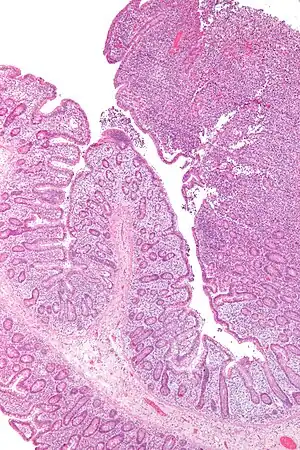

| Micrograph of an enteropathy-associated T-cell lymphoma (upper right of image), a type of T-cell lymphoma. H&E stain. | |